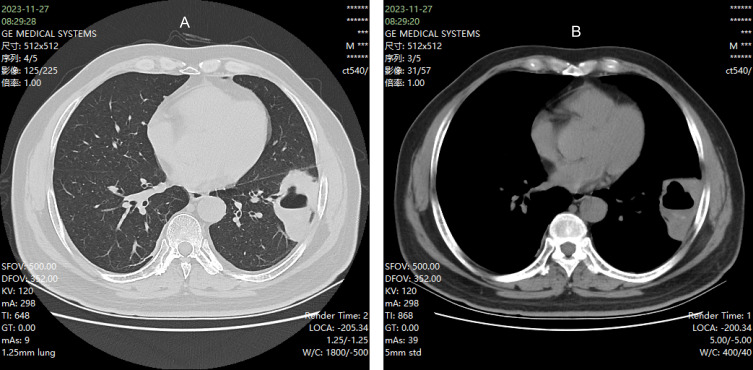

Complete blood count and high-sensitivity C-reactive protein (hs-CRP): The complete blood count revealed a white blood cell count of 14.6× 109/L, with neutrophils at 10.2×10−9/L and lymphocytes at 3.1×10−9/L. hs-CRP was elevated at 79.4 mg/L. Procalcitonin levels were below 0.04 ng/mL. Glycosylated hemoglobin (HbA1c) was measured at 8.1%. Interleukin-6 levels were elevated at 20.95 pg/mL, and ferroprotein levels were significantly increased at 1115.81 ng/mL. Sputum cultures, both aerobic and anaerobic, conducted over a 5-day period, yielded no bacterial growth. A chest computed tomography (CT) scan (Figure 1) revealed a cystic lesion with fluid levels and localized lung involvement in the left lung.

Figure 1.

(A and B) Chest CT before treatment.